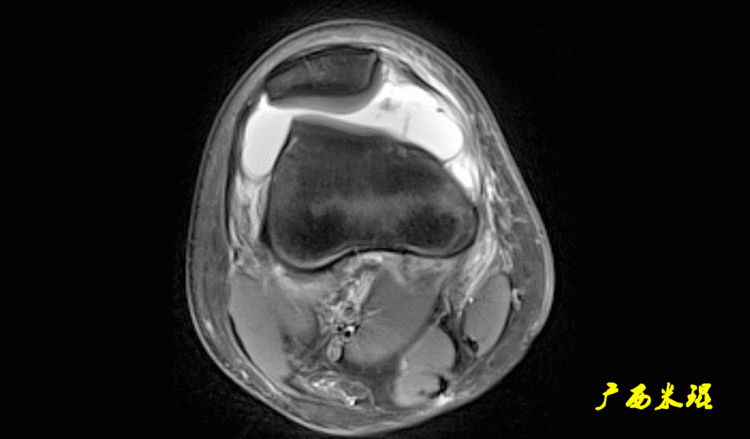

MRI检查是最常用的评估髌股关节软组织和滑车软骨的检查,在发现MPFL损伤时具有较高的敏感性和准确性,其特征性表现包括X线不能发现的软骨损伤及髌骨内侧面和股骨外侧髁的骨挫伤。MRI也可用于评估髌骨滑车指,测量髌骨高度等。